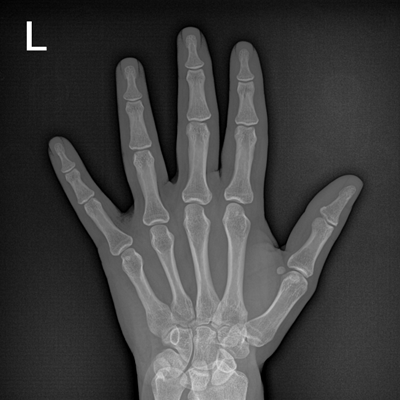

● 數(shù)字化無線平板成像,操作簡便,成像質(zhì)量高